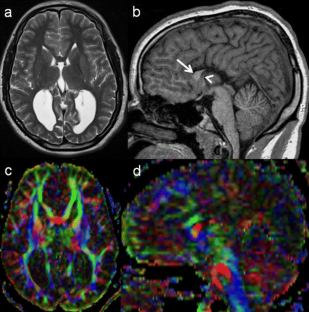

Fig. 1